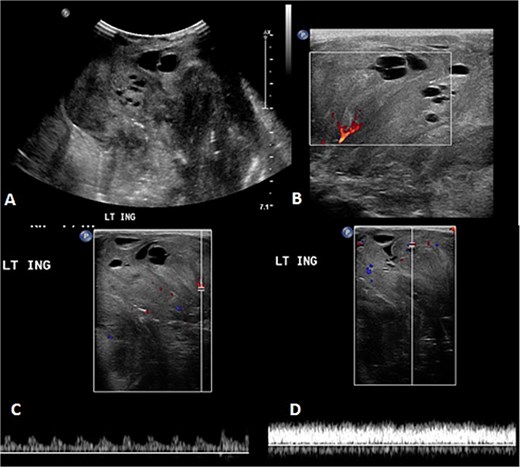

A 2-month-old girl was being followed for a suspected hemangioma on her left hand since birth. She was initially started on oral propranolol therapy but only received one dose, due to family concerns about possible side effects. The patient presented at the emergency room because of ulceration. It was observed clinically that the lesion had grown from 1.5 × 1.5 cm to 4 × 2 cm (Fig. 5). A biopsy of the lesion was taken. Ultrasound showed a partially defined large heterogeneously hyperechoic mass with internal vascularity on color Doppler with arterial and venous waveform giving atypical features of hemangioma (Fig. 6). Biopsy was done using FoundationOne Heme. The result showed stable microsatellite status and when we tested the tumor mutational burden, it showed two mutations per megabase. On MRI, a large lobulated subcutaneous soft tissue mass measuring 3.7 × 6.1 × 4.6 cm in dimensions was seen originating from the medial aspect of the left hand (Fig. 7). Internal flow voids, intermediate signal intensity on T1-weighted images, hyperintense signal on short tau inversion recovery (STIR)-weighted images, and noticeable heterogeneous enhancement on postcontrast sequences were all observed in the lesion. These imaging results raised suspicions of a malignant lesion.

MRI of left hand mass. (A) Axial T1WI shows a huge homogenous isointense mass to the corresponding hand muscles signal intensity, which is seen along the medial aspect of left hand. (B and C) Coronal STIR demonstrate heterogeneous diffuse high signal intensity of the lesion and appears inseparable with sign of invasion to the fourth and fifth digits extensor compartment/tendons as well as presence of areas of signal void (arrow). (D and E) Axial and sagittal post-contrast T1 fat-saturated images show diffuse progressive intense enhancement of the lesion.